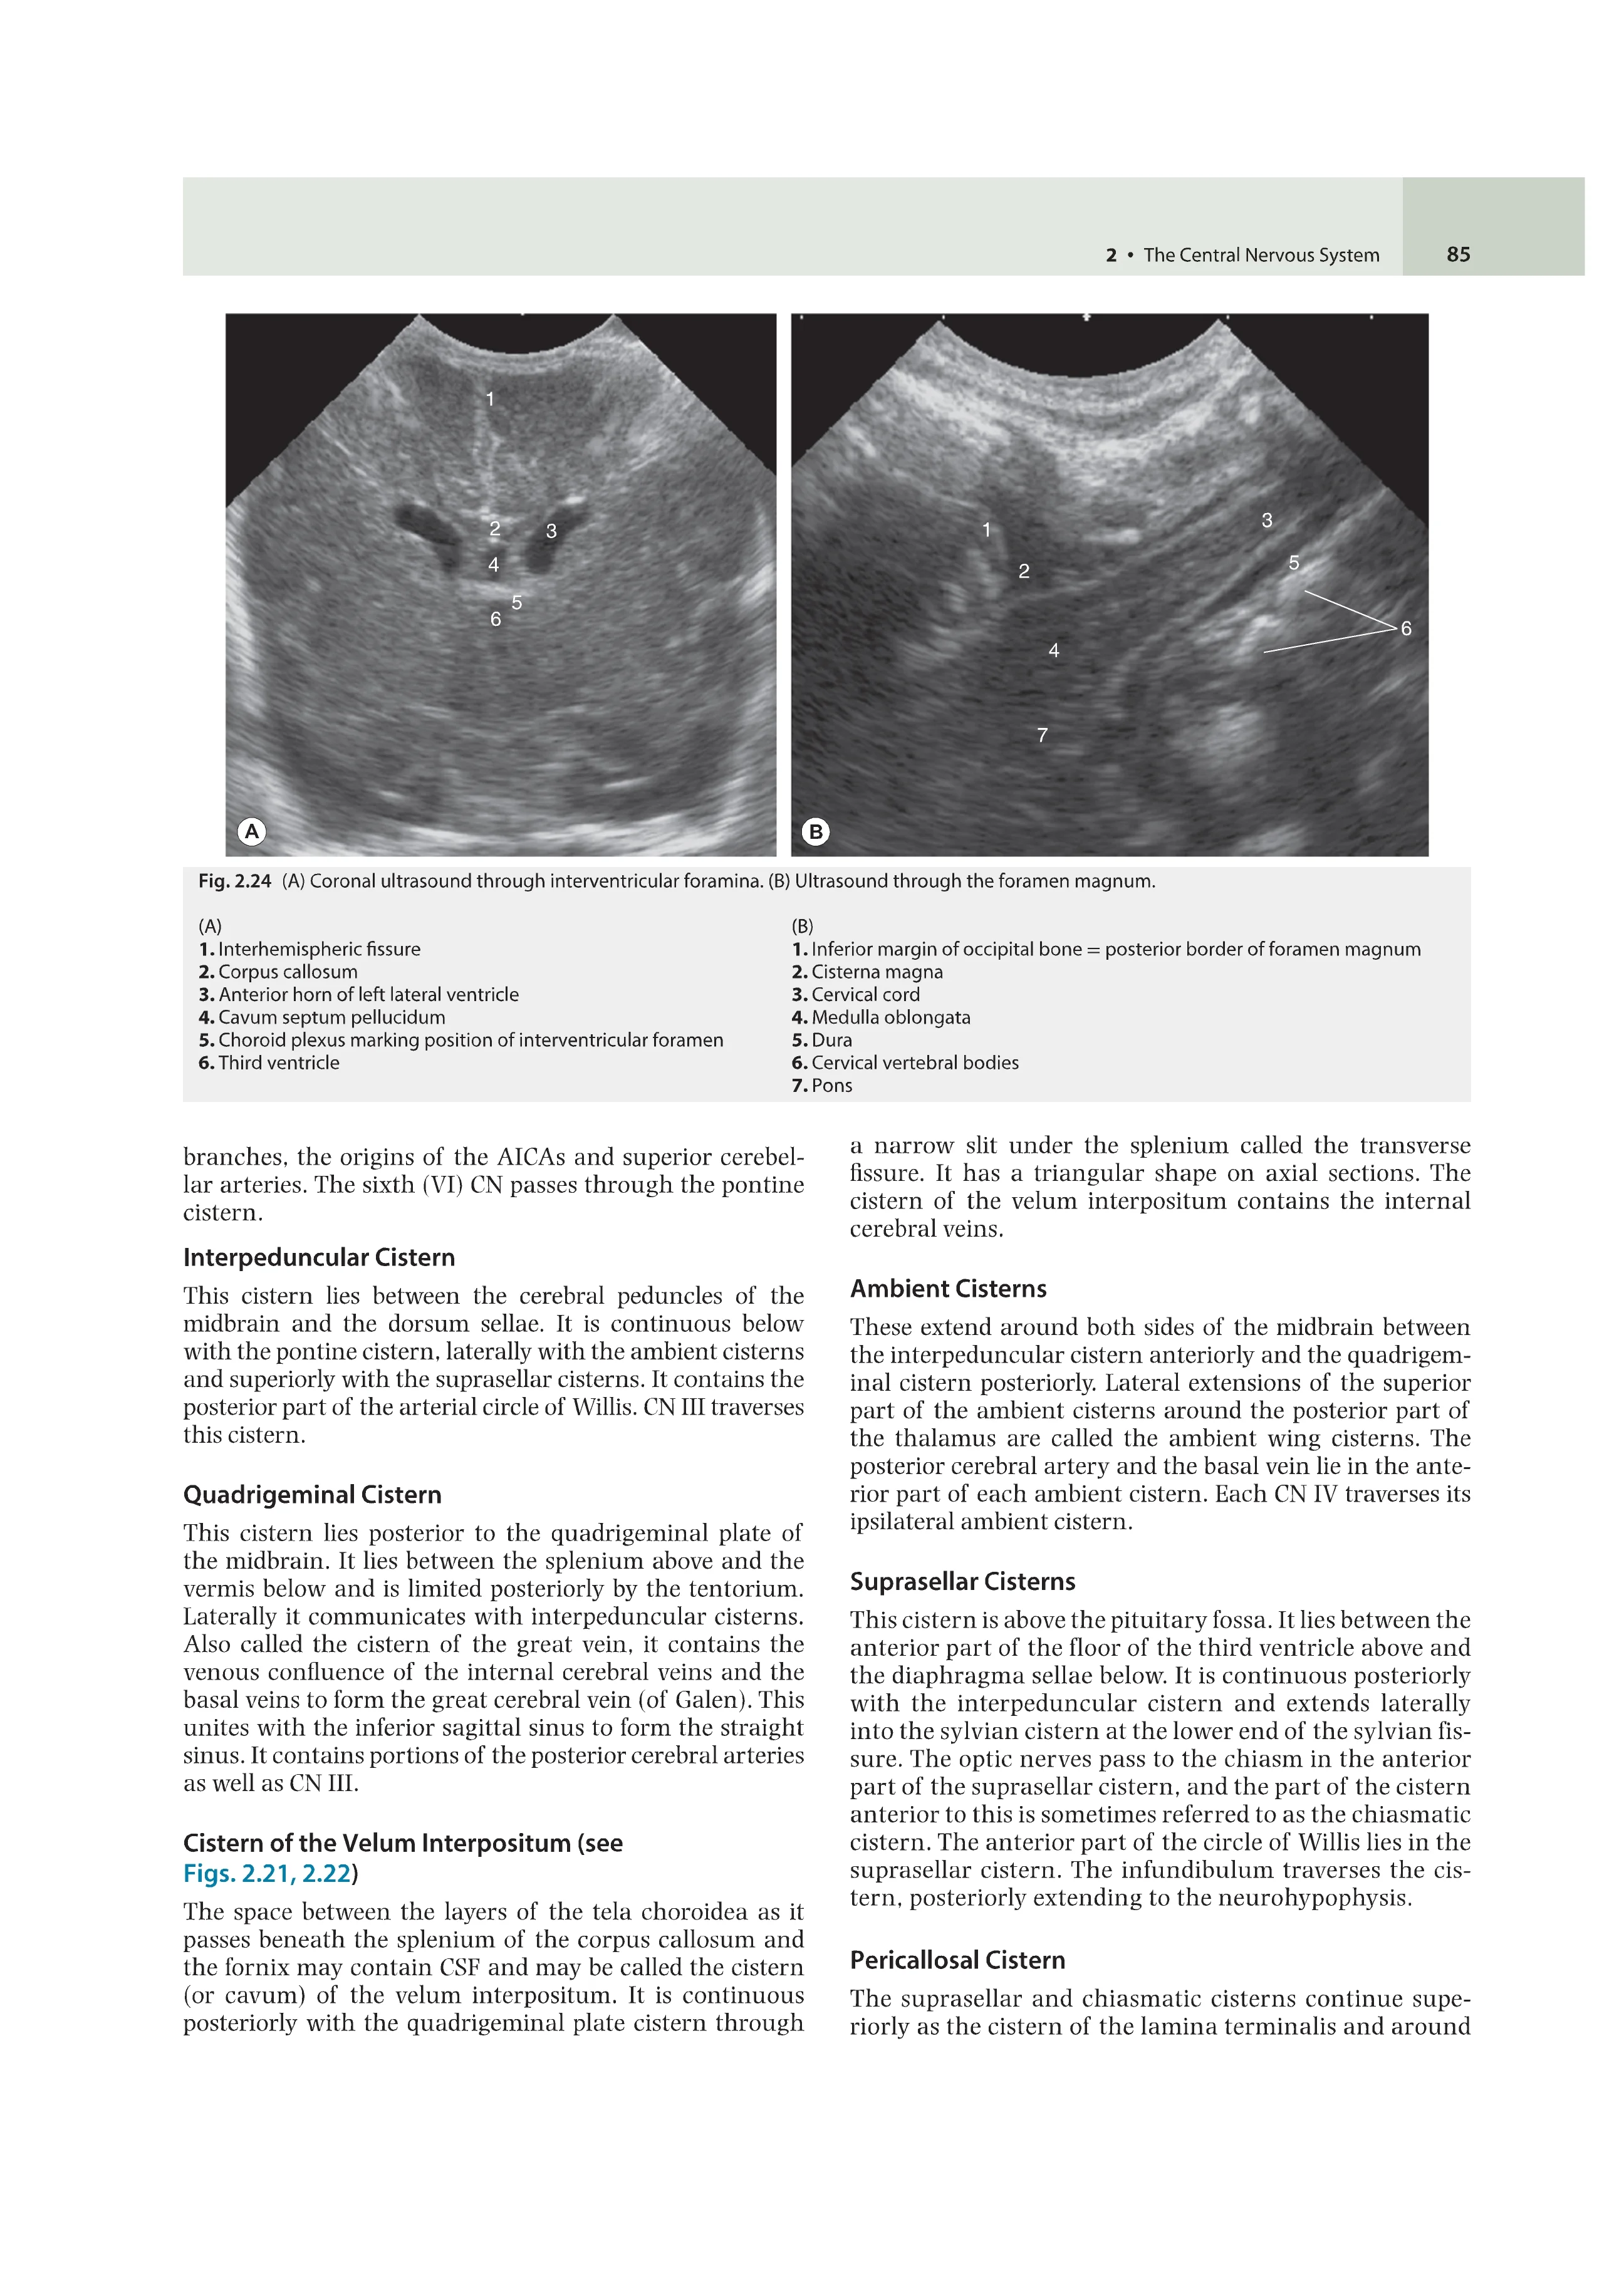

Иллюстрации: Цветные и черно-белые

Anatomy for Diagnostic Imaging, Fourth Edition covers everything trainee radiologists need to know about anatomy shown in the full range of medical imaging, including CT, MR and ultrasound.

It provides an initial traditional anatomical description of each organ or system, followed by the radiological anatomy of that part of the body with labelled imaging examples in all modalities. A series of 'radiology pearls' emphasises clinically and radiologically important points.

Written by radiologists with immense clinical and teaching experience, with seven new contributors, the fourth edition has been fully updated reflecting advances in imaging and evolving clinical practice. It will be indispensable for radiology registrars and residents, especially candidates for postgraduate radiology exams. A manageable size, it will also be of great use to radiographers, medical students, physicians, surgeons and others whose work requires an understanding of radiological anatomy. It is also an extremely useful reporting station reference book.

Provides key images in all modalities